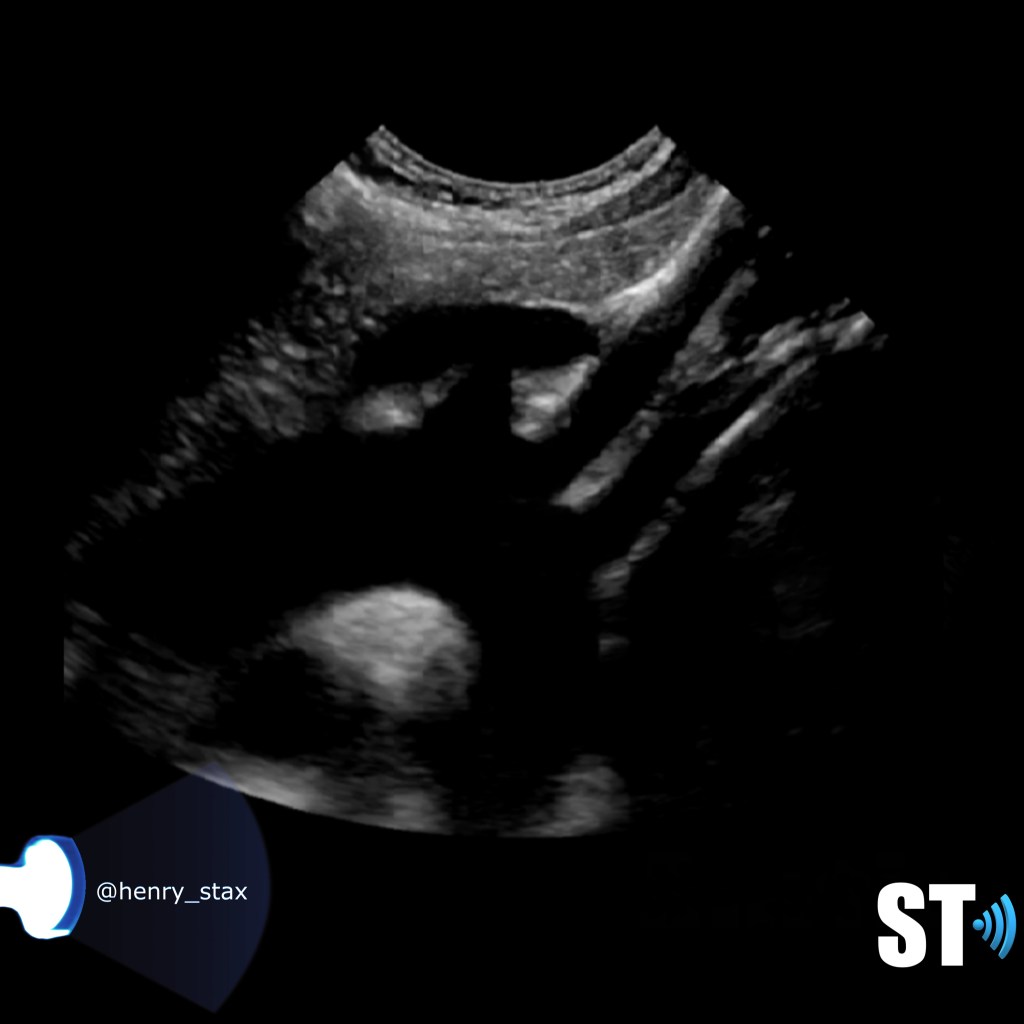

The aorta is the main artery of the body arising from the outflow tract of the left ventricle. It is shaped like an umbrella handle or a candy cane. The first portion is the ascending aorta which then curves to become the aortic arch. Here there are three consecutive vessels that arise and course cephalad. The first is the brachiocephalic or innonimate artery which further bifurcates into right subclavian and common carotid arteries. Next is the left common carotid artery followed immediately by the left subclavian artery.

The subclavian artery arises from the brachiocephalic artery on the right and off of the aortic arch on the left. This artery further divides into the axillary, brachial, radial, ulnar, palmar and digital arteries respectively.